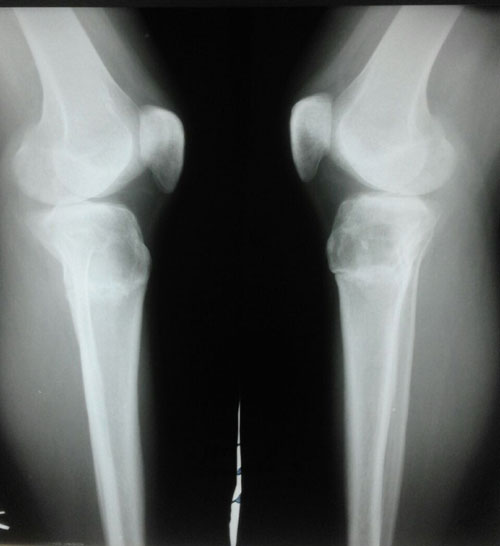

рентген в 90 дней.

Пора на снятие аппаратов!